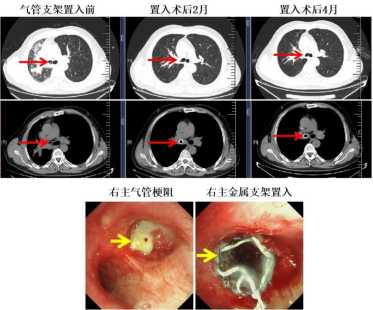

87岁的李爷爷是小细胞肺癌晚期患者,肿瘤疯狂生长压迫主气道,老人连说话都成了奢望,血氧饱和度一度跌至70%。家属抱着最后一丝希望找到赵主任:“只要能让老人喘上气,我们愿意尝试!”

呼吸介入团队仅用30分钟完成大气道金属支架置入术,撑开被肿瘤挤压的“生命通道”,老人当场咳出积痰,血氧迅速回升。后续治疗中,团队充分考虑高龄患者的耐受性,采用免疫联合伊立替康脂质体方案——既避免了传统化疗的严重骨髓抑制,又激活了老人的免疫应答。如今,李爷爷已带瘤生存半年余,每天还能自行外出遛弯。

核心技术亮点:高龄患者紧急气道支架置入术快速救命,老年肿瘤个体化免疫联合方案平衡疗效与安全性。

“医生,我爸坚决不做化疗!”半年前急诊抢救室里,出租车司机丁师傅红着眼眶恳求。他的父亲69岁,肺鳞癌晚期伴大气道狭窄,呼吸困难已无法平卧,却因对化疗副作用的恐惧拒绝全身治疗。

“先救命,再谈治疗。”赵主任团队当机立断,急诊行气道金属裸支架置入术,1小时内解除梗阻危机。后续沟通中,团队结合患者“保生活质量”的诉求,制定免疫联合抗血管治疗的“无化疗”方案——免疫治疗激活自身抗癌力,抗血管生成药物切断肿瘤血管营养供给。治疗3周期后,老人不仅呼吸顺畅,肿瘤标志物也大幅下降,如今每月复查一次,状态越来越好。

核心技术亮点:急诊气道介入技术化解急危重症,免疫联合抗血管生成方案实现“去化疗化”精准治疗。